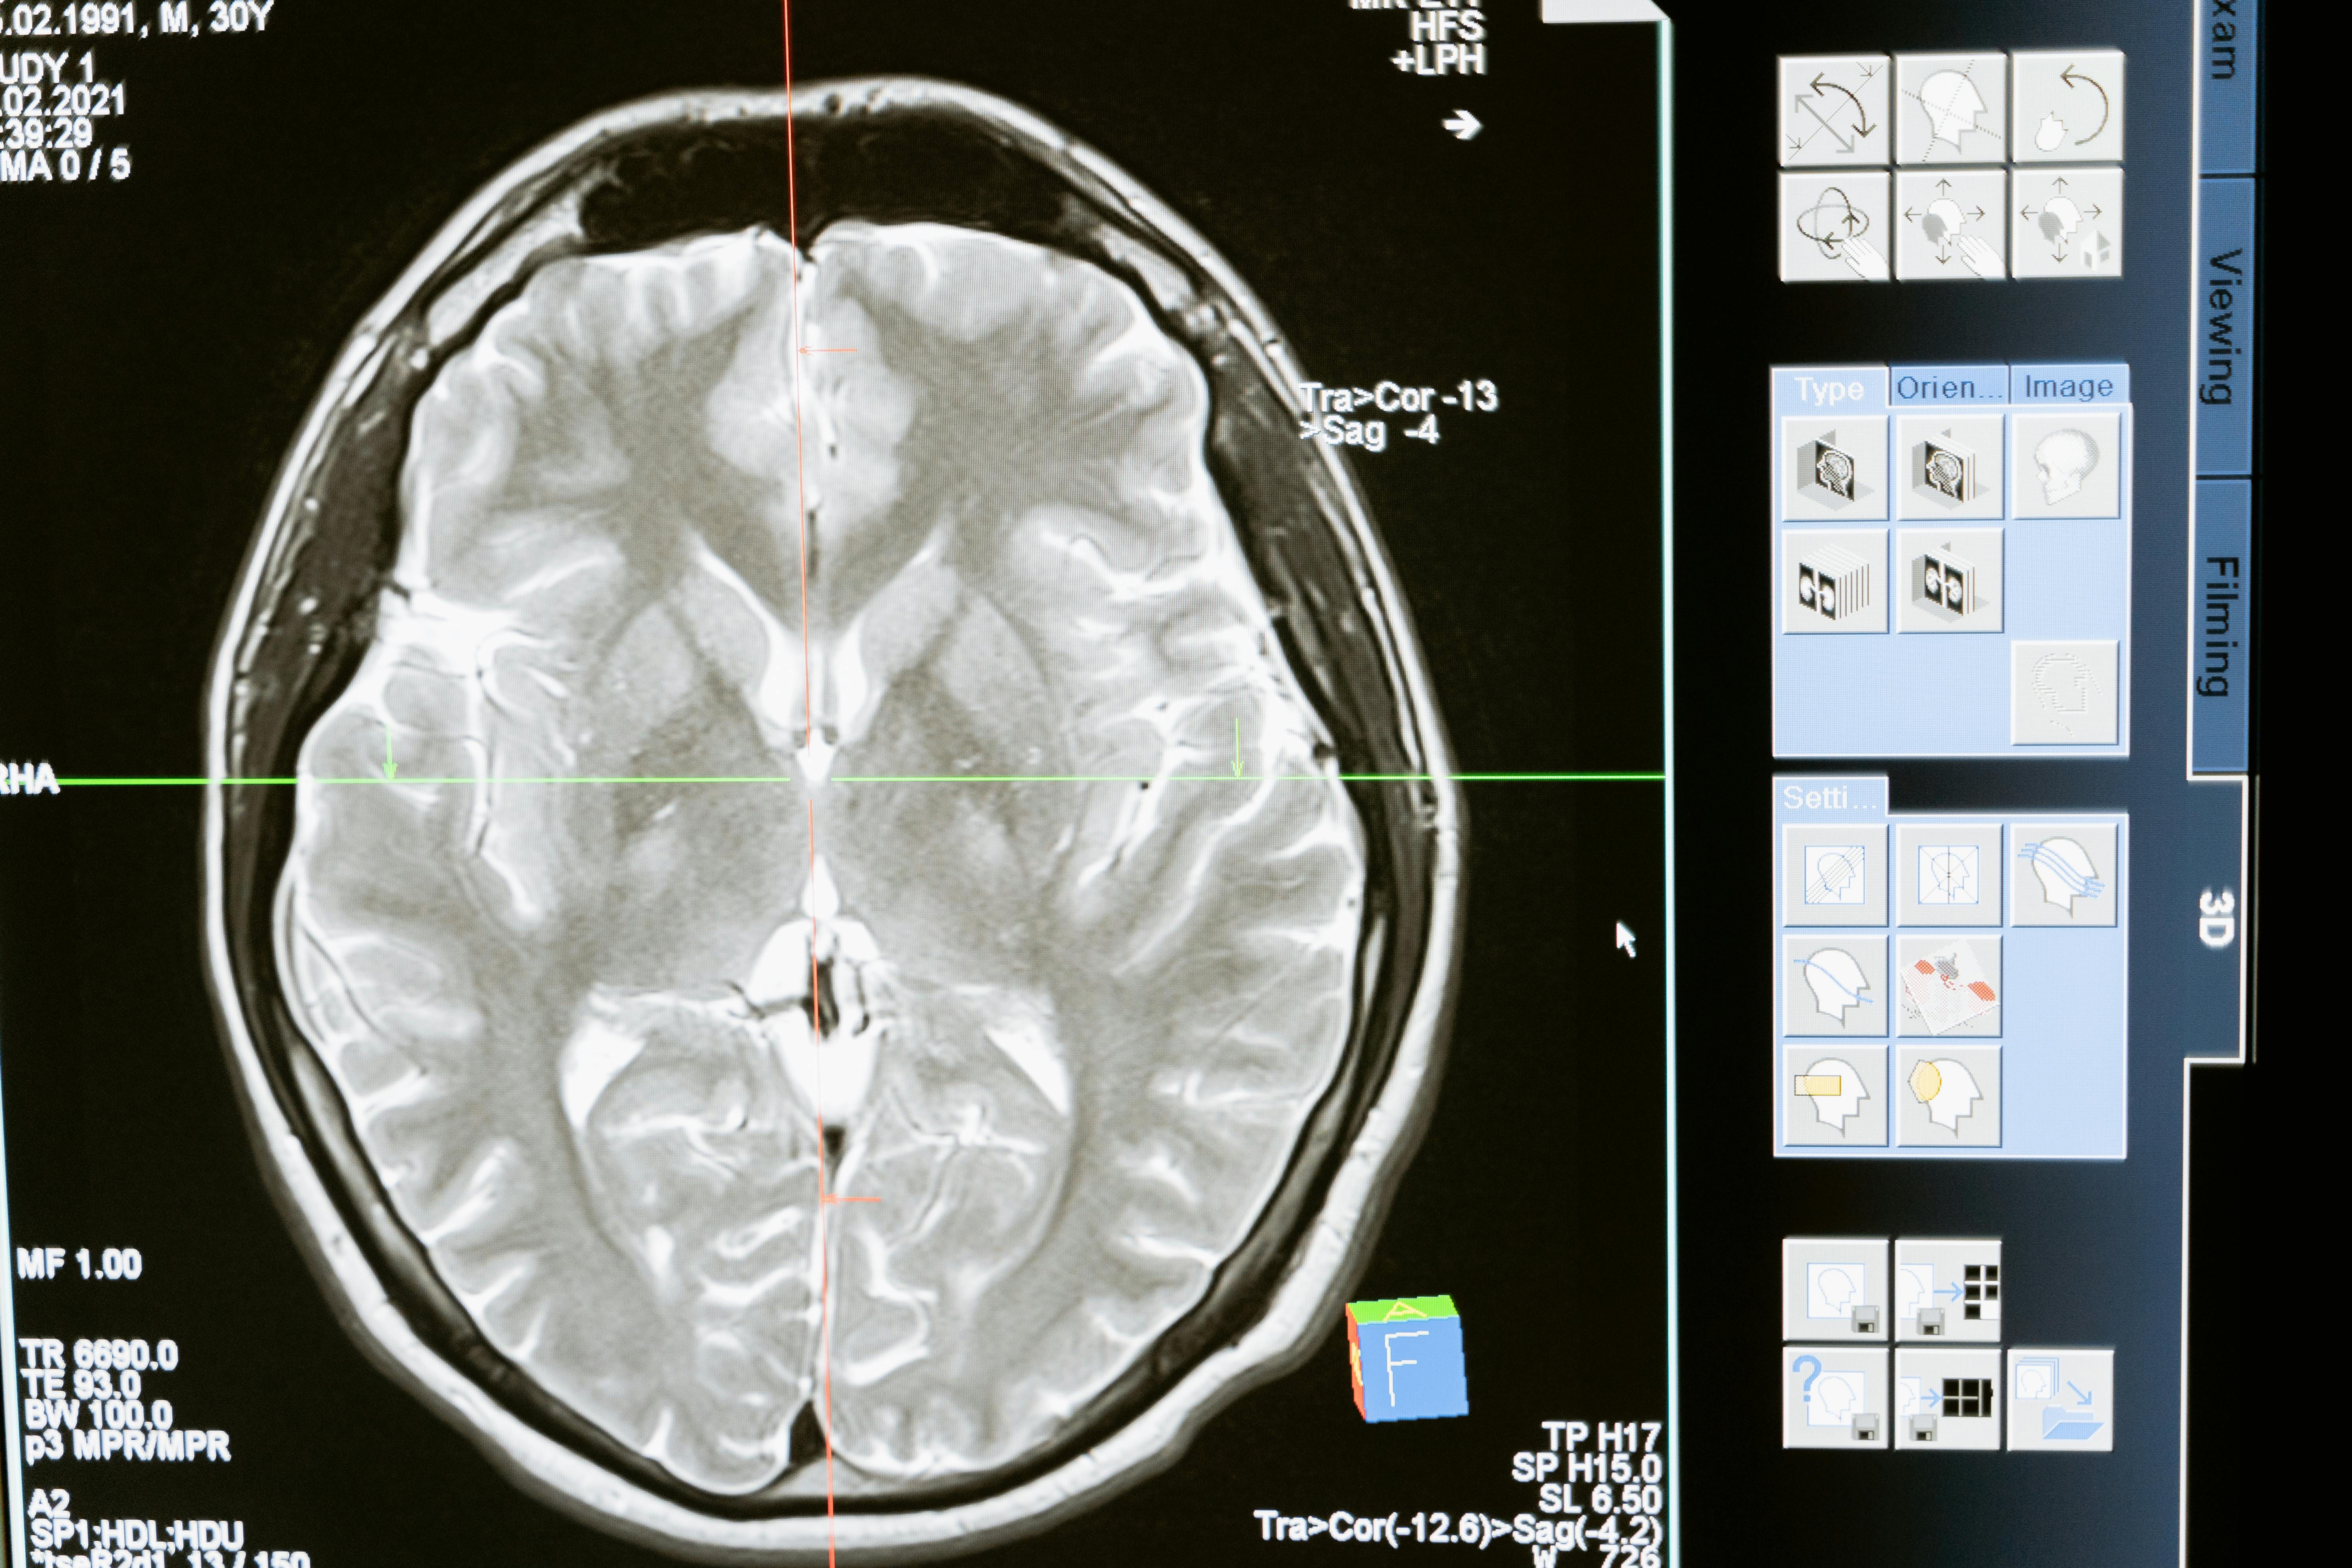

Turns out, you’re not alone and you’re not broken. You’re just a human with a brain. And according to neuroanatomist Jill Bolte Taylor, your brain is basically a house with four wildly different roommates. Each one has their own voice, their own personality, and their own agenda. And yes, they all think they should be in charge.

Jill Bolte Taylor, that incredible neuroanatomist who turned her own stroke into a superpower of insight. Her ideas on the brain’s four characters have me geeking out, and I bet they’ll spark some aha moments for you too. Think of it as your brain hosting its own quirky ensemble cast, each with a role in the daily drama of life.

First off, if you haven’t caught Jill’s TED Talk Jills Ted Talk or grabbed her book Whole Brain Living, do yourself a favour. She breaks down the brain into four distinct characters based on how our left and right hemispheres process the world. It’s not just left brain logical, right brain creative anymore. She splits each side into thinking and emotional parts, creating this fabulous quartet that drives our choices, moods, and basically everything.